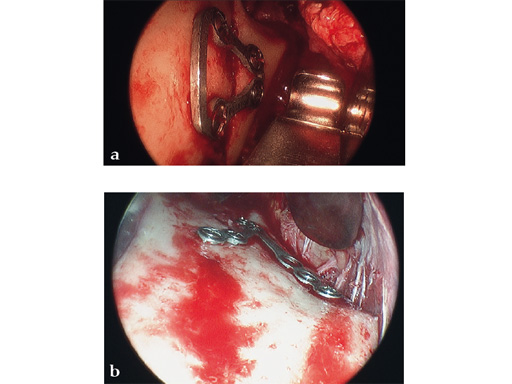

Case 1

Case provided by Celso Palmieri, Shreveport, LA, USA

Case 2

Case provided by Michael Rasse, Innsbruck, Austria